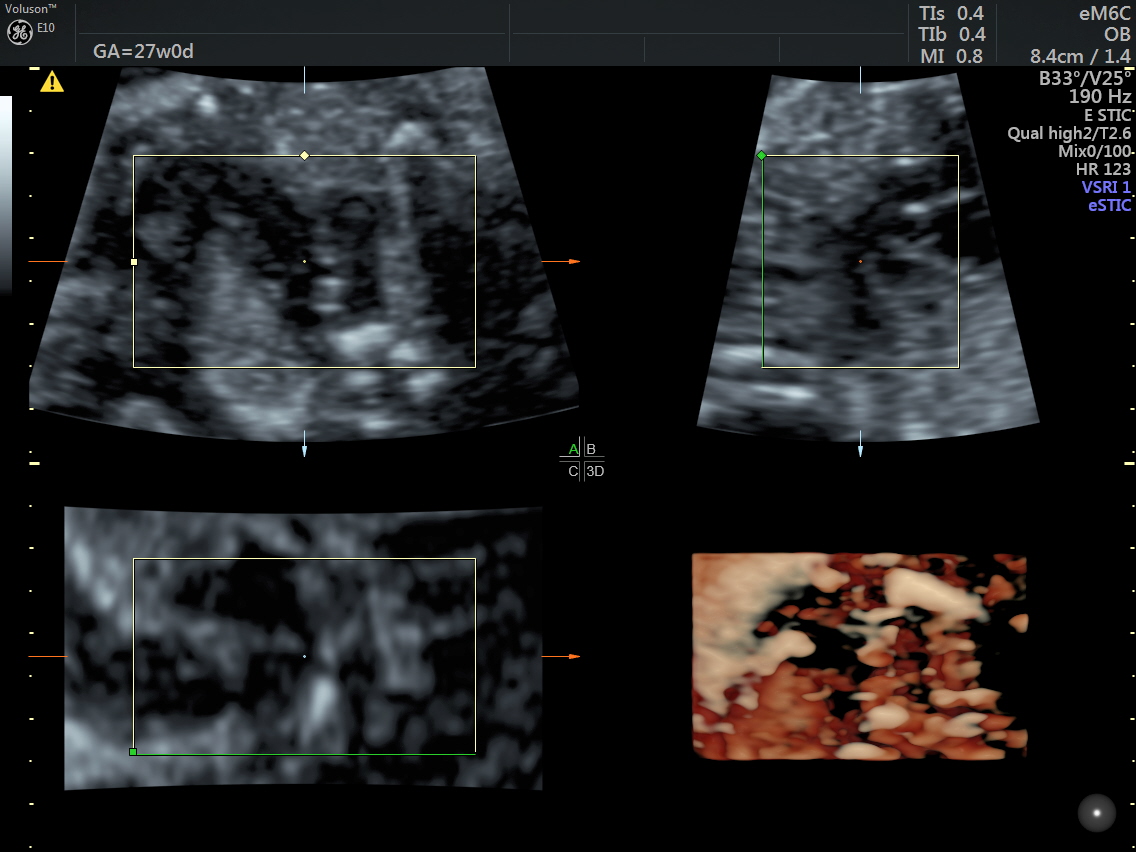

RT AORTIC ARCH_20 Published June 17, 2016 at 1136 × 852 in Rt aortic arch and aberrant left subclavian artery ← Previous Next →